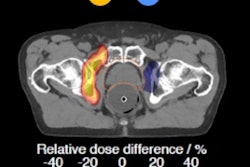

Figure 1: For protons and other ions the peak of energy loss occurs just before the particles reach a halt. This is called the Bragg peak, first put to use at Lawrence Berkeley Laboratory to treat the first patient with protons in 1954.However, if one looks at the dose deposition profile of photons compared with other particles (figure 1), the conspicuous feature of this graph is that, in the case of protons and carbon ions, a significant fraction of the energy is deposited in a narrow depth range near the endpoint of the trajectory, after which very little energy is deposited. It was precisely these differences in dose -- the so-called Bragg-peak effect -- that led visionary physicist and founder of Fermilab, Robert Wilson, to propose the use of hadrons for cancer treatment in 1946.

Hadron or particle therapy is a precise form of radiotherapy that uses charged particles instead of x-rays to deliver a dose of radiotherapy to patients. Radiation therapy with hadrons or particles (protons and other light ions) offers several advantages over x-rays: Not only do hadrons and particles deposit most of their energy at the end of their range, but particle beams can be shaped with great precision. This allows for more accurate treatment of the tumor, destroying the cancer cells more precisely with minimal damage to surrounding tissue. Radiotherapy using the unique physical and radiobiological properties of charged hadrons also allows highly conformal treatment of various kinds of tumors, in particular those that are radio-resistant.